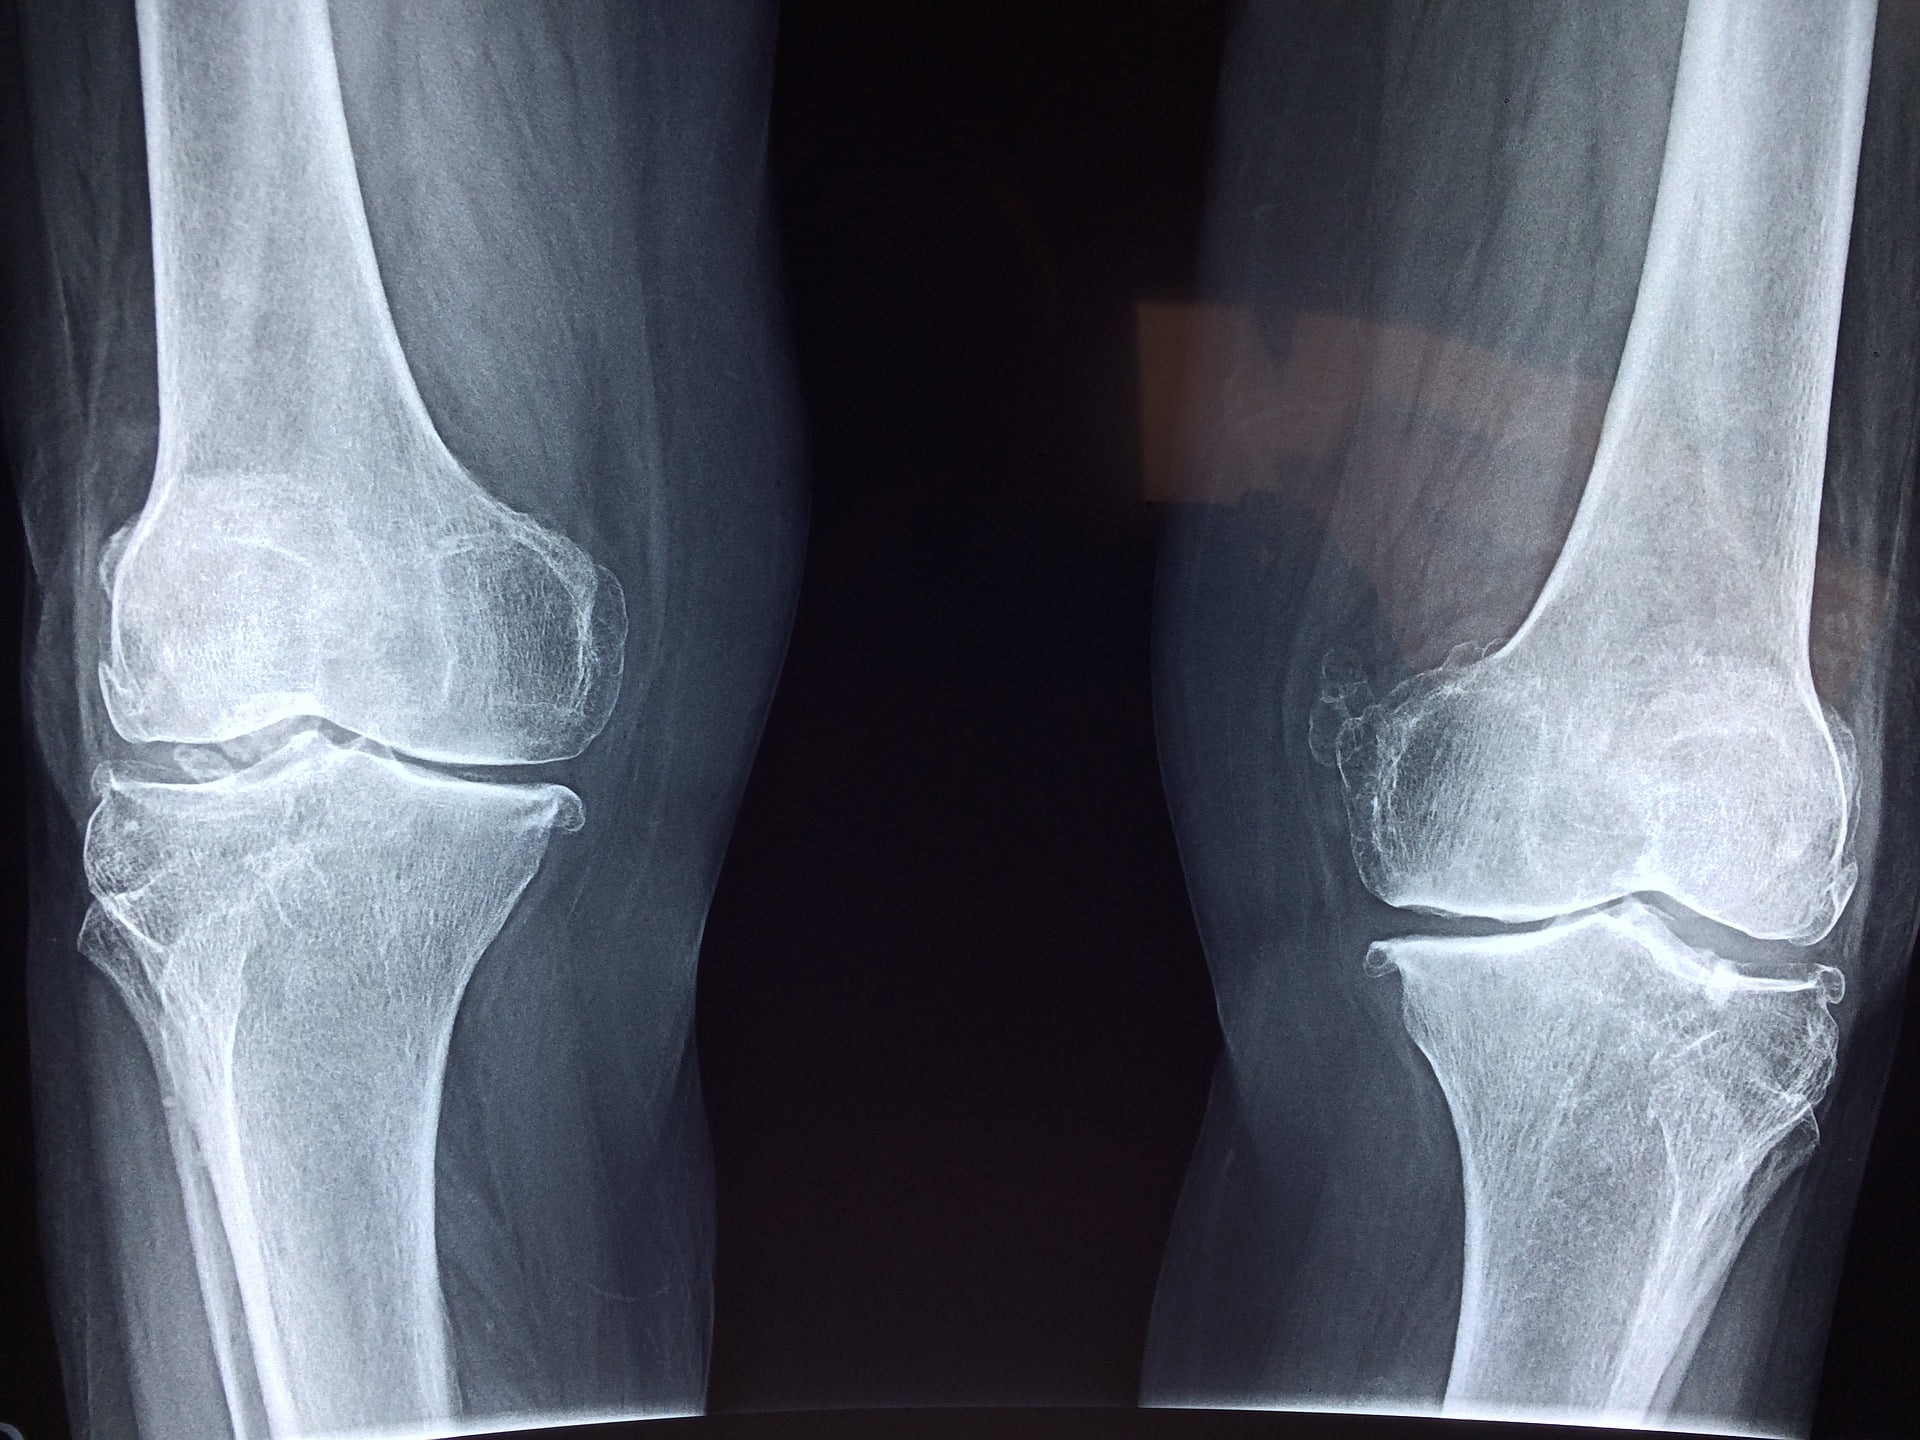

LA TENDINITE AL POLPLITEO Il popliteo è un muscolo rotatore interno della tibia e coinvolto nella stabilizzazione del ginocchio. Viene particolarmente sollecitato in tutte le